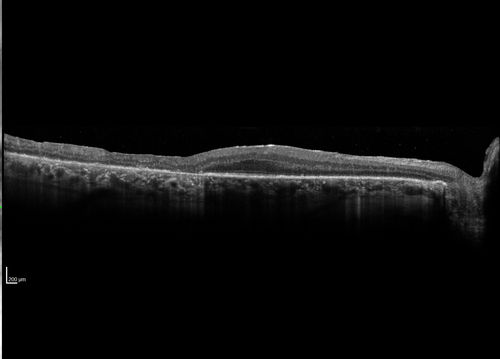

Severe outer retinal atrophy and RPE non-geographic atrophy from syphilis.  Vision improved from 20/63 to 20/32 with therapy.  Images look a lot like DUSN.  Patient had several surgeries (vitrectomy for floaters, vitrectomy for macular pucker, Avastin injections and macular laser for edema) prior by other retina specialists prior to being correctly diagnosed and treated.

Syphilitic Chorioretinitis